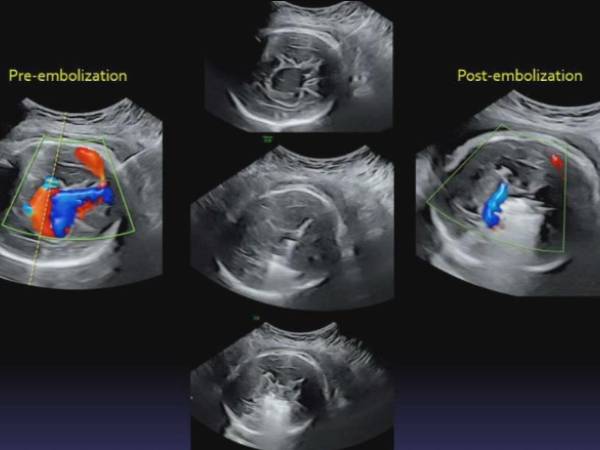

அப்போது அவர்களுக்கு மிகப் பெரிய அதிர்ச்சி காத்திருந்தது. குழந்தைக்கு மூளையிலிருந்து இதயத்திற்கு ரத்தத்தை எடுத்துச் செல்லும் ரத்த நாளங்கள் வளர்ச்சி அடையாமல் இருந்தது தெரியவந்தது. இதனால் அங்கிருந்து இதயத்திற்கு அதிக ரத்தம் செல்வதை கண்டறிந்தனர். இது போன்ற பாதிப்புகள் என்பது Vein of Galen malinformation என கூறப்படுகிறது. இந்த நிலை தொடர்ந்தால் கருவில் இருக்கும் சிசுவுக்கு உயிருக்கே ஆபத்து. ஒரு வேளை குழந்தை பிறந்தாலும் அது சில காலம் மட்டுமே உயிர்வாழும் என மருத்துவர்கள் தெரிவித்தனர்.

தாயின் வயிற்றில் சிறிய துளையிட்டு ஊசி போன்ற சிறிய கருவியின் மூலம் தலையில் துளையிட்டு பின்னர் எலக்ட்ரிக் காயில் போன்று இருக்கும் ஒரு கருவி மூலம் குழந்தையின் ரத்த நாளங்களை சரி செய்துள்ளனர். இதனால் மூளையிலிருந்து இதயத்திற்கு செல்லும் அதிகபடியான ரத்தம் குறைந்தது. இனி குழந்தைக்கு எந்த ஆபத்தும் இல்லை என மருத்துவர்கள் கூறியதால் தாயும் தந்தையும் மகிழ்ச்சி அடைந்தனர்.